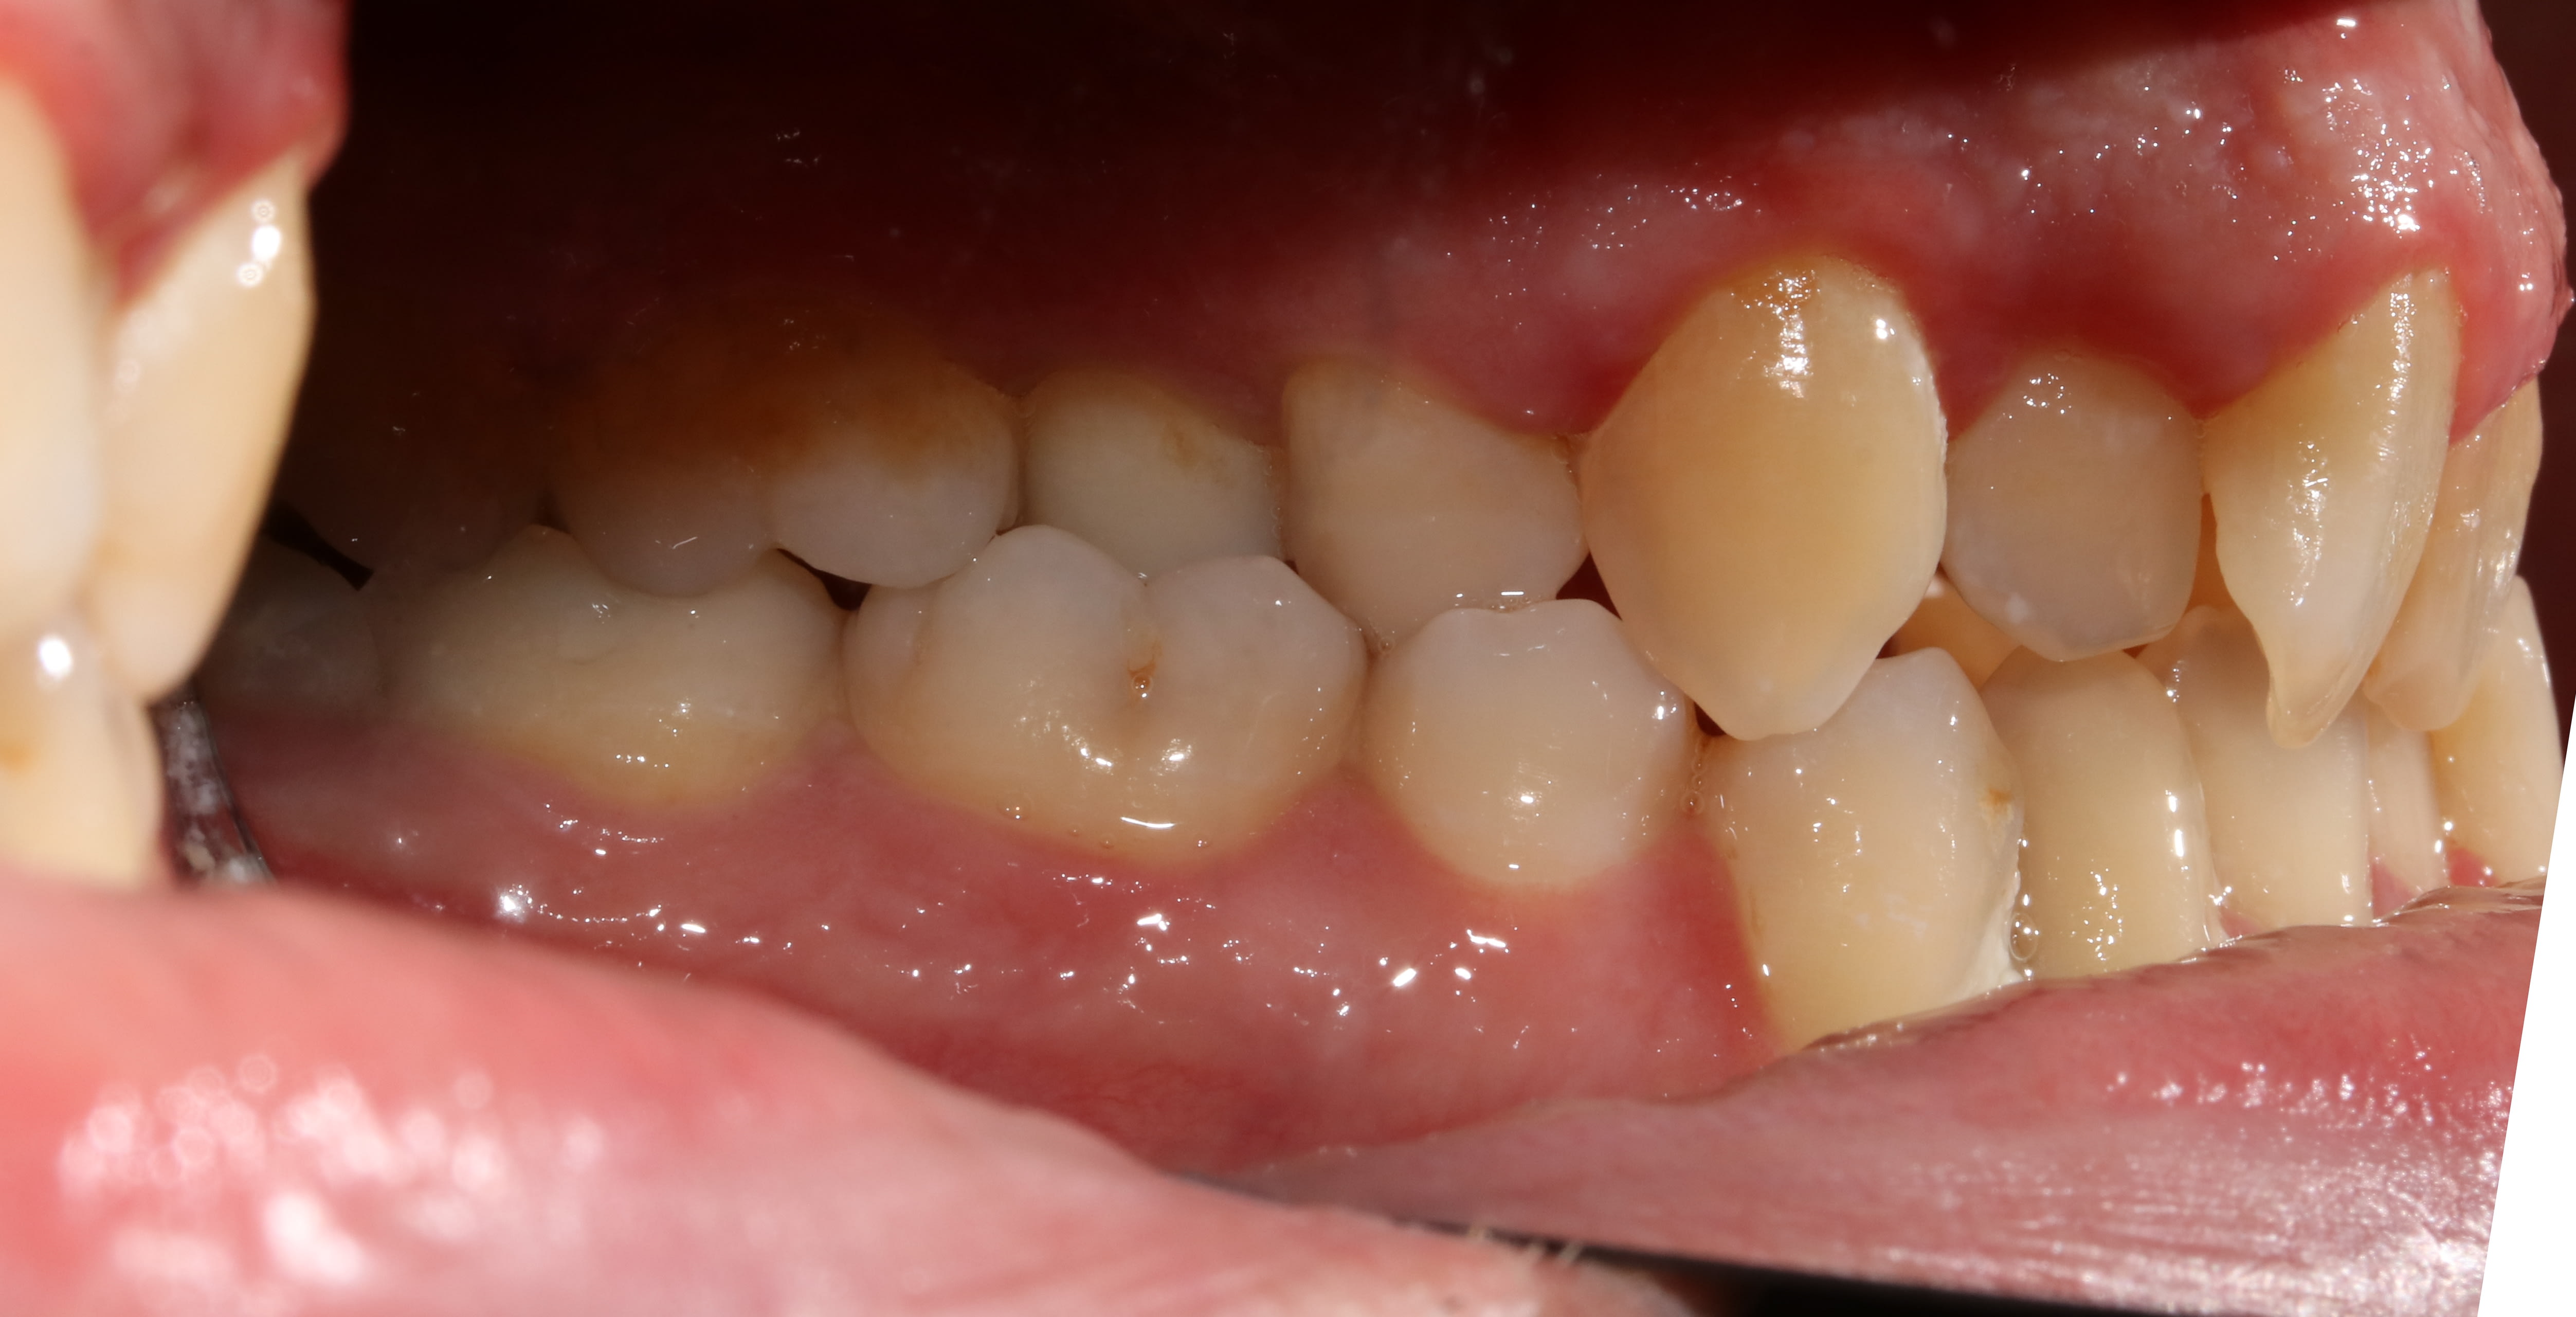

36 ans ...un oublié de l'ortho ...

Droite njf4pn - Eugenol

Face pyrsyz - Eugenol

Gauche snbsdh - Eugenol